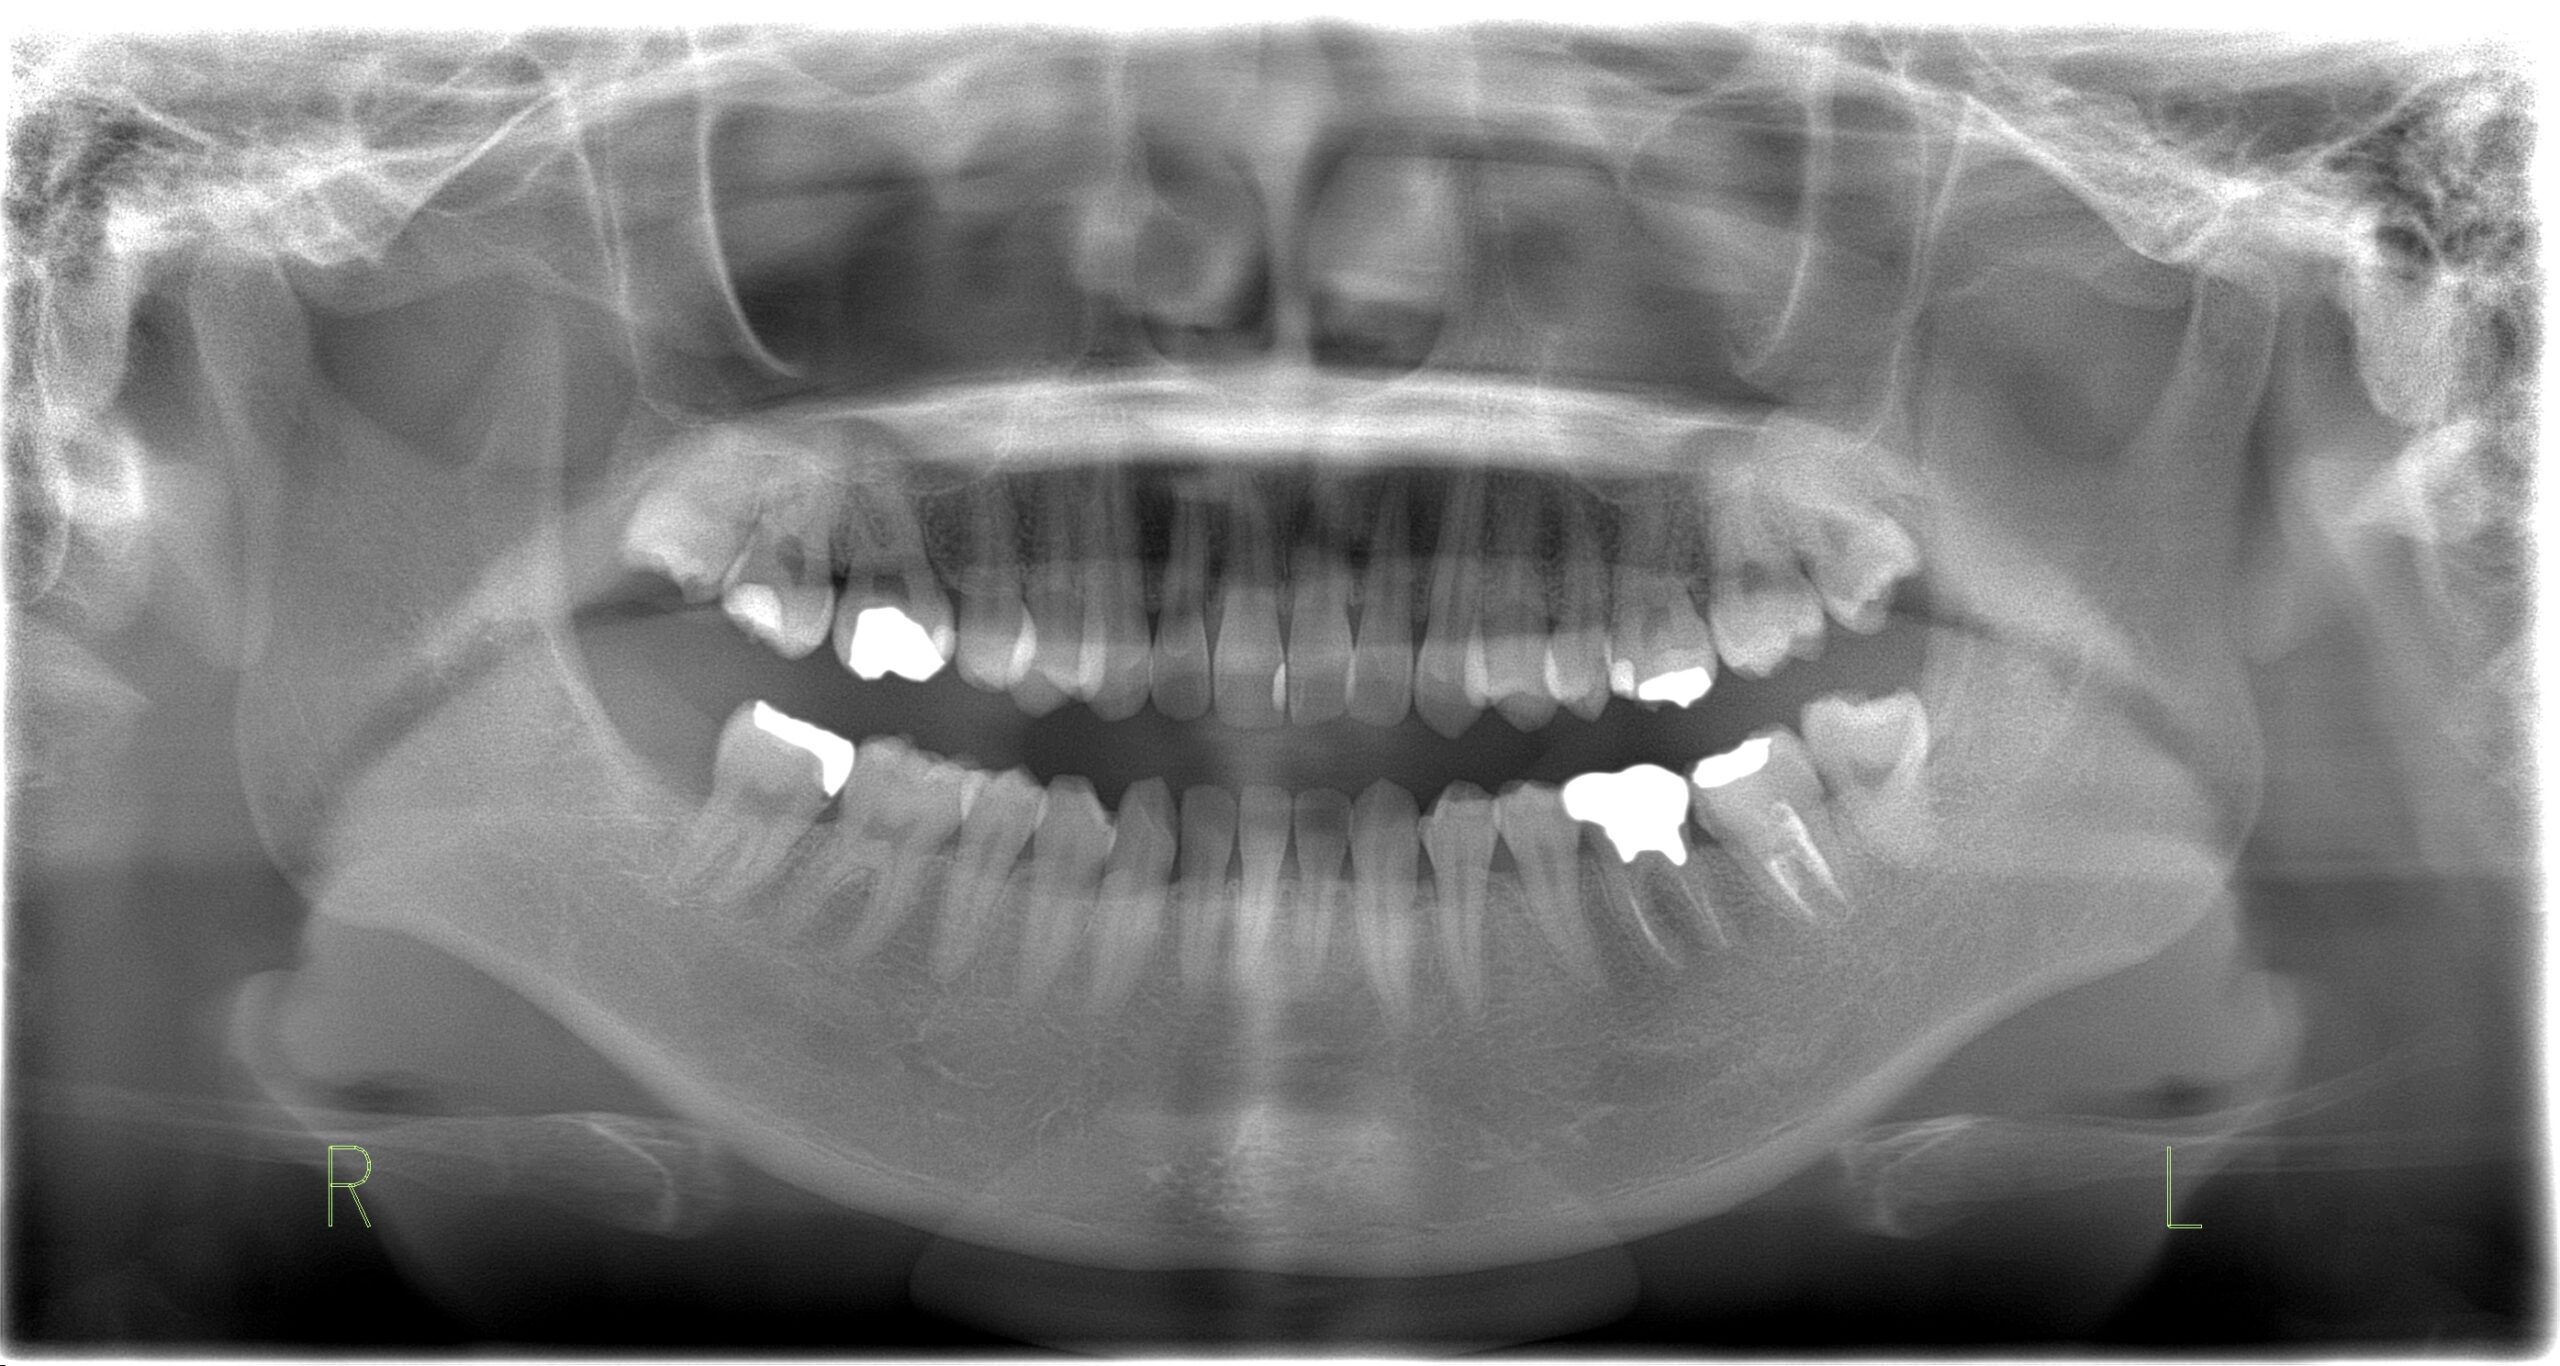

小児矯正 プレオルソ 10歳男の子

Before

-

After

主訴 かみあわせが反対になっている 診断名 前歯部反対咬合 年齢・性別 10歳 男性 治療期間・回数 4か月 4回 治療方法 プレオルソというマウスピース型の機能的矯正装置を使用して、歯並び・かみあわせを改善しました。 費用 11万円 デメリット・注意点 ・自分で取り外し可能な装置なので、装置を入れないと矯正は進みません。

・症例によっては改善しない場合もあります。

・歯に力が加わるので多少の痛みを伴います。

・矯正治療終了後、しっかり保定しないと後戻りをする場合があります。 -